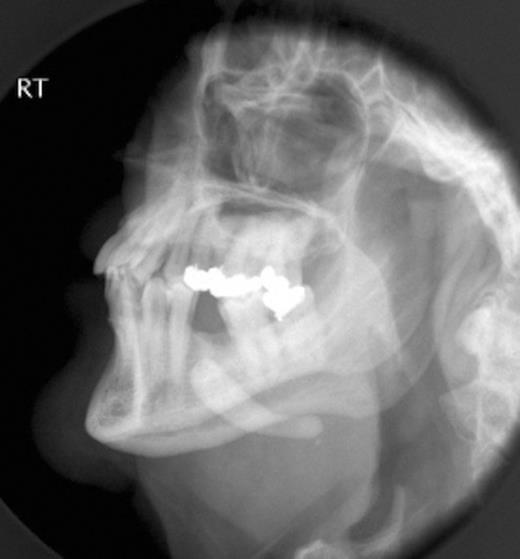

Plain radiograph demonstrating large radiopaque submandibular mass

Clinical examination revealed right submandibular swelling and tenderness, with a large salivary calculus palpable in the right floor of mouth. The presence of the sialolith was confirmed on plain radiograph (Fig. 1) with a large opaque mass being evident in the right submandibular region.